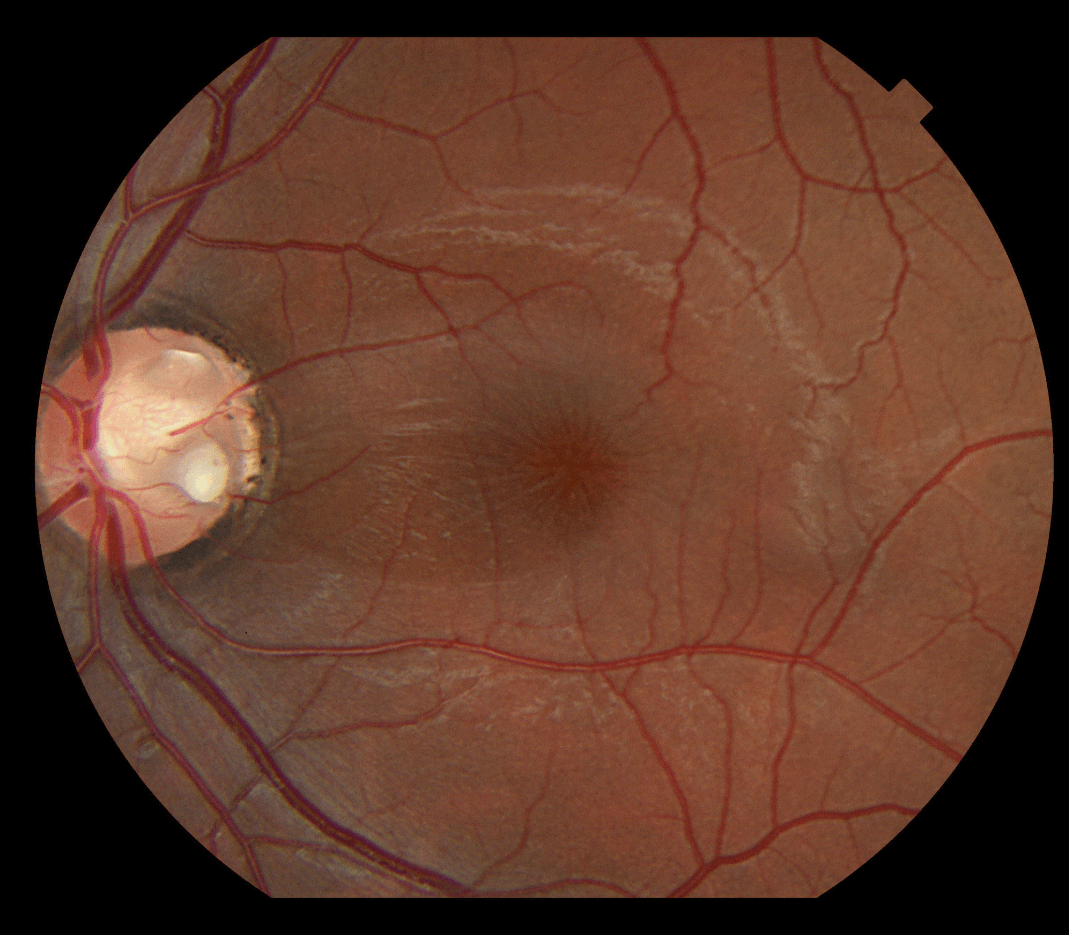

This OCT image shows a retinal condition impacted by the vitreous.

What is VMT?